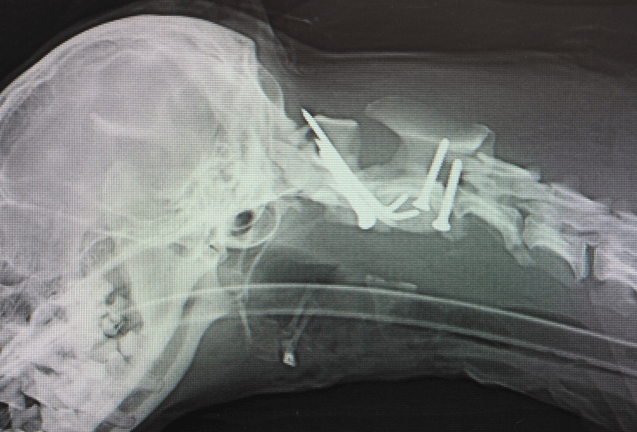

同じように、椎弓切除からの椎体固定と同じノリで、開頭してプレートいれてしまう事もあります。これは神経科というか腫瘍科根性でしょうか。リハビリのヤツと同じで、意味のない称号かなんかわからん腫瘍科認定医もあまり好きではないです。一部だと思うんですけど全然腫瘍とらん腫瘍科もいます。